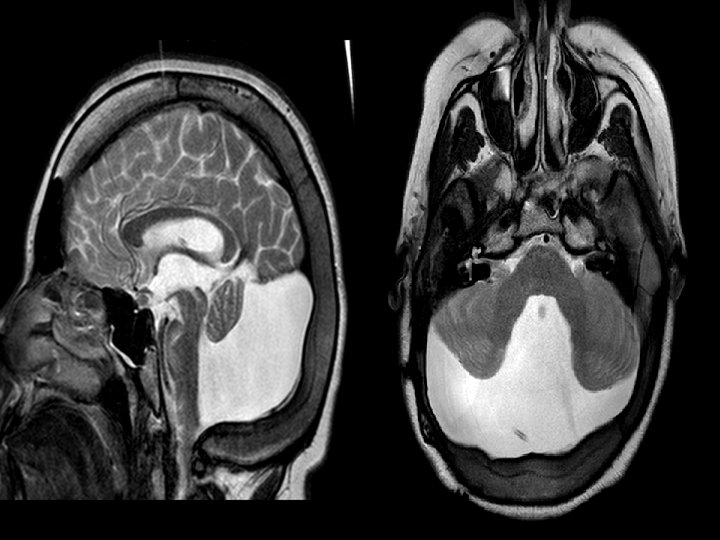

Aksial T 2 ve sagital T 1 MRT: Arxa çuxuru genişləndirən ve 4. mədəcik ilə əlaqəli kista görülür ve hipoplastik beyincik izlənməktədir.

T 1 sagital kəsikdə arxa çuxurda böyük ölçülü kista, hipoplastik soxulcan kist üzərində yuxarıya çevrilib. Beyincik yarımkürələri və beyin kötüyü hipoplastikdir, incəlmiş ənsə pulu

T 2 şəkildə hidrosefaliya, arxa çuxurda böyük BOM kistası incəlmiş ənsə sümüyü və hipoplastik beyincik yarımkürələri qanad şəkilli